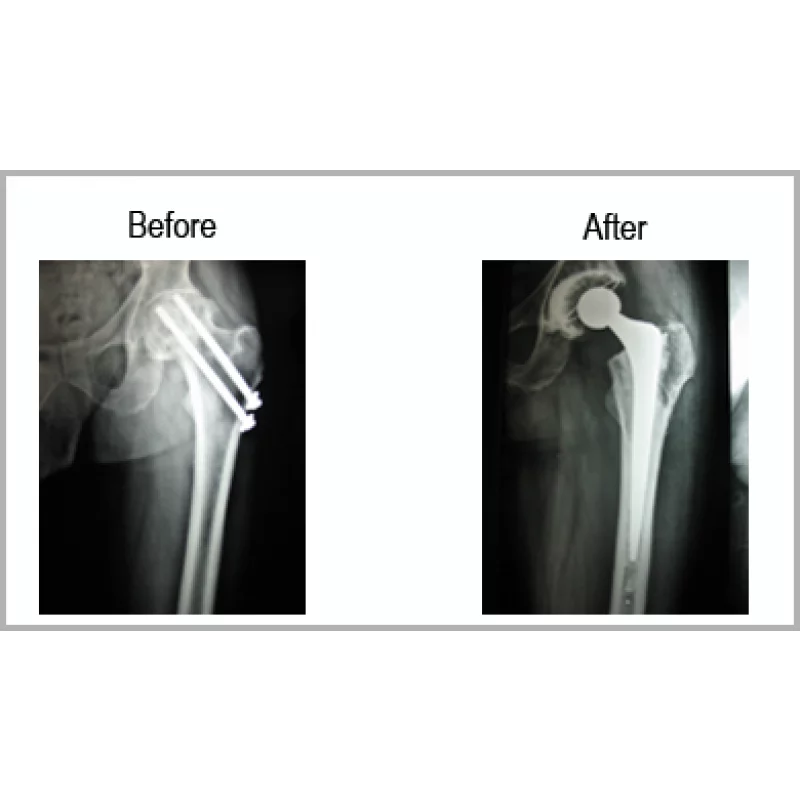

A Male Aged 50 Years Was Operated For Left Neck Femur Fracture By Screw Fixation. He Developed AVN. He Had Great Difficulty In Walking And Performing Daily Activities.He Underwent Implant Removal And Total Hip Replacement. Now Absolutely Pain Free And It Is Difficult To Make Out That He Has Been Operated For Left Hip.... Read more